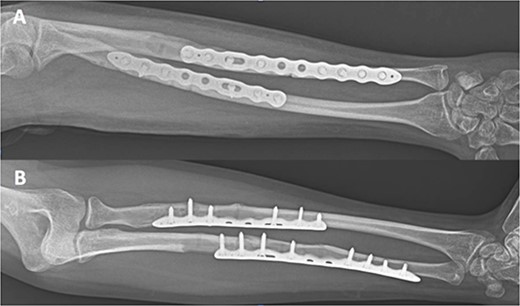

A 32-year-old male was referred to the emergency room after a sport accident. Fourteen months previously, he successfully underwent osteosynthesis with two 3.2 mm stainless steel locking plate (Trimed Elbow Forearm System™, CA, USA) for a radial (six-holes) and ulnar (seven-holes) shaft fractures after a sport accident. On admission, X-rays revealed a NPPIF of both forearm bones (Fig. 1), classified as P1A type [2]. The fracture was just distal to the edge of the last screw of both plates. The patient underwent both hardware removal, reduction of the fractures and fixation using two 3.5 mm longer titanium dynamic compression plate for the radial (eight holes) and ulnar (10 holes) shaft fracture (Stryker Corporation Kalmazoo, MI, USA). After that, the patient was referred for physical therapy and rehabilitation. A total of 3 months after surgery, complete bone healing was observed (Fig. 2). At final follow-up, 36-months after surgery, the patient’s elbow extension and flexion was from 0° to 130°, wrist pronation and supination was from 90° to 75°, and wrist flexion and extension were 75° and 70° were completely painless. His grip strength was 93% that of the opposite hand.

Type P1A fracture—well healed original fracture with NPPIF of both forearm bones distal to the tip of the implant.

Internal fixation of both NPPIFs with a longer plate that bridges the original fracture zone and the new NPPIF. Final follow-up at 36 months after surgery, anterior–posterior X-ray.